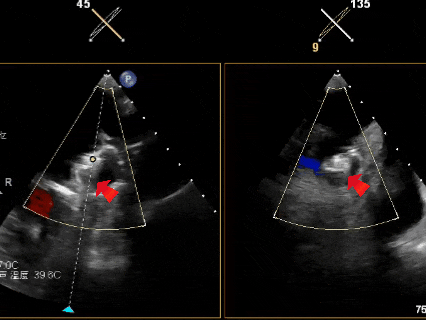

常规经食道超声心动图(TEE)评估发现,左心耳血流速度明显减慢,流速约 24 cm/s,提示存在血栓形成高风险因素,但左心耳内未见自发显影。此外,TEE发现巨大房间隔膨胀瘤(ASA,大小约28×10mm),同时合并卵圆孔未闭(PFO),且ASA腔内可见明显自发性显影(SEC),其内血流速率明显减慢(20.8cm/s)。

左心耳排空速度测量

巨大房间隔膨胀瘤及自发显影